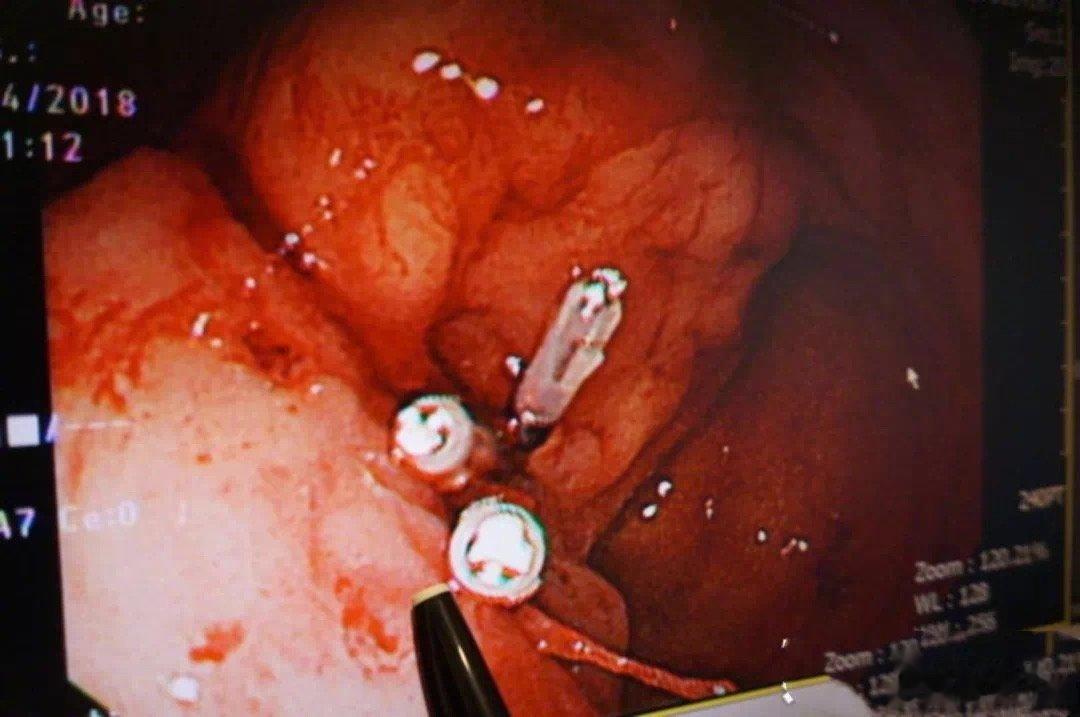

图片2:胃镜下给他在三个出血点上了血管夹来止血

医生赶紧在胃镜下给他在三个出血点上了血管夹来止血。受益于现代的医疗技术,男生转危为安了。